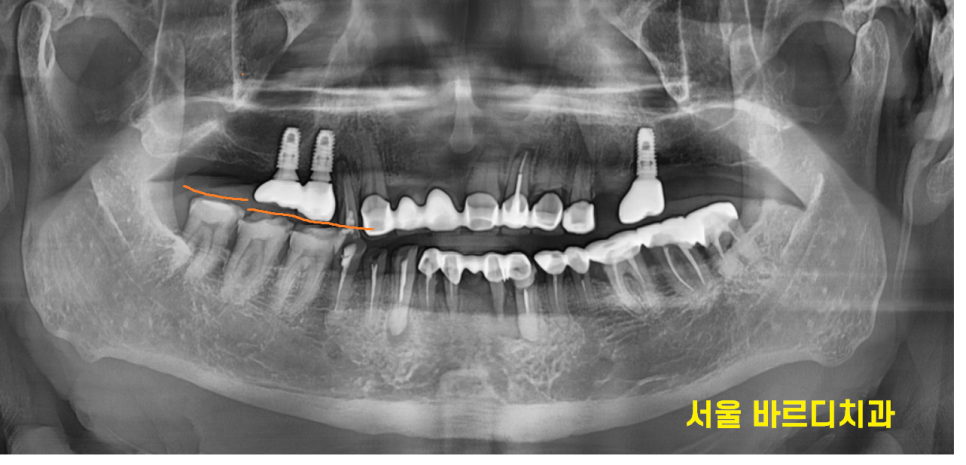

두번째 문제점은 나중에 임플란트를 하게 되었을 때

높이가 나오지 않게 될 수 있습니다.

무슨 말이냐하면..

231019

반대편 치아 올라옴으로 앙 물었을 때

높이가 안나오는거죠~

이렇게 되면 임플란트를 해도

보철 머리 길이가 짧아지거나

반대편 치아를 신경치료 후

보철을 할 때 치아를 깎아 높이를 맞춰주거나...

해야합니다.